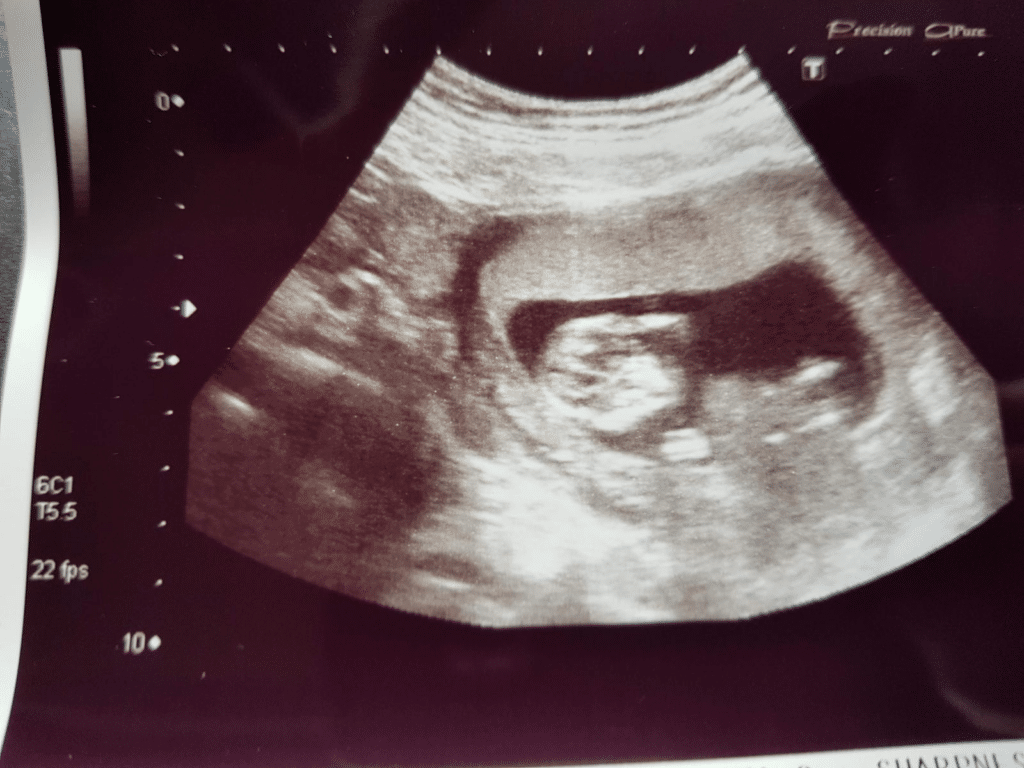

“40 en zwanger van mijn 1e.”

Na een succesvol pleegzorgtraject en de zorg voor een weekendkindje, bleek er een onverwacht wonder op haar pad: zwanger op haar 40ste. Na een zware zwangerschap werd hun zoon geboren, en zijn leven kent sindsdien ups en downs. Een bijzondere reis vol uitdagingen en liefde.